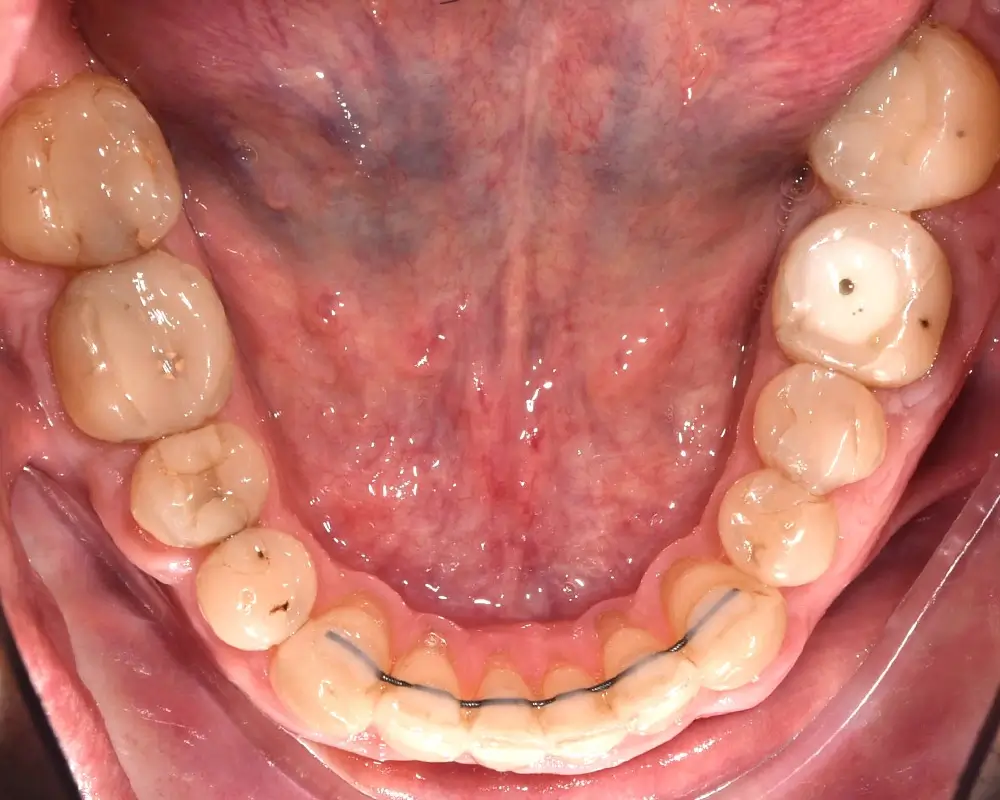

Мезиальный прикус - Кейс 7

Эффективность устранения дефекта прикуса посредством элайнеров FlexiLigner.

Количество кап НЧ

Результаты лечения